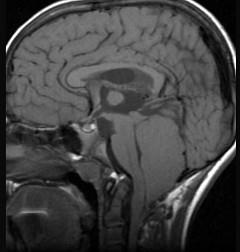

问题 第四脑室室管膜瘤(如图所示)临床特点包括()

选项 A.颅内高压症状较早 B.多以头痛为首发症状 C.伴有呕吐、头晕及强迫头位 D.肿瘤增大累及小脑蚓部或半球时,可出现平衡障碍、步态不稳和共济失调等 E.当肿瘤压迫脑干或脑神经时,可出现相应的脑神经障碍

答案 ABCDE